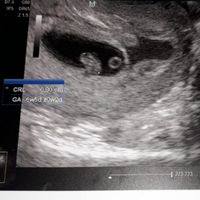

Ciao ragazze, Oggi ho fatto la traslucenza nucale e la dottoressa mi ha detto che il fagiolino era in posizione impeccabile,tanto che il tubercolo si vedeva benissimo e mi ha detto femmina al 100%. Io...

Ciao ragazze, Oggi ho fatto la traslucenza nucale e la dottoressa mi ha detto che il fagiolino era in posizione impeccabile,tanto che il tubercolo si vedeva benissimo e mi ha detto femmina al 100%. Io già da ramzi avevo predetto femmina, ma aspettavo...